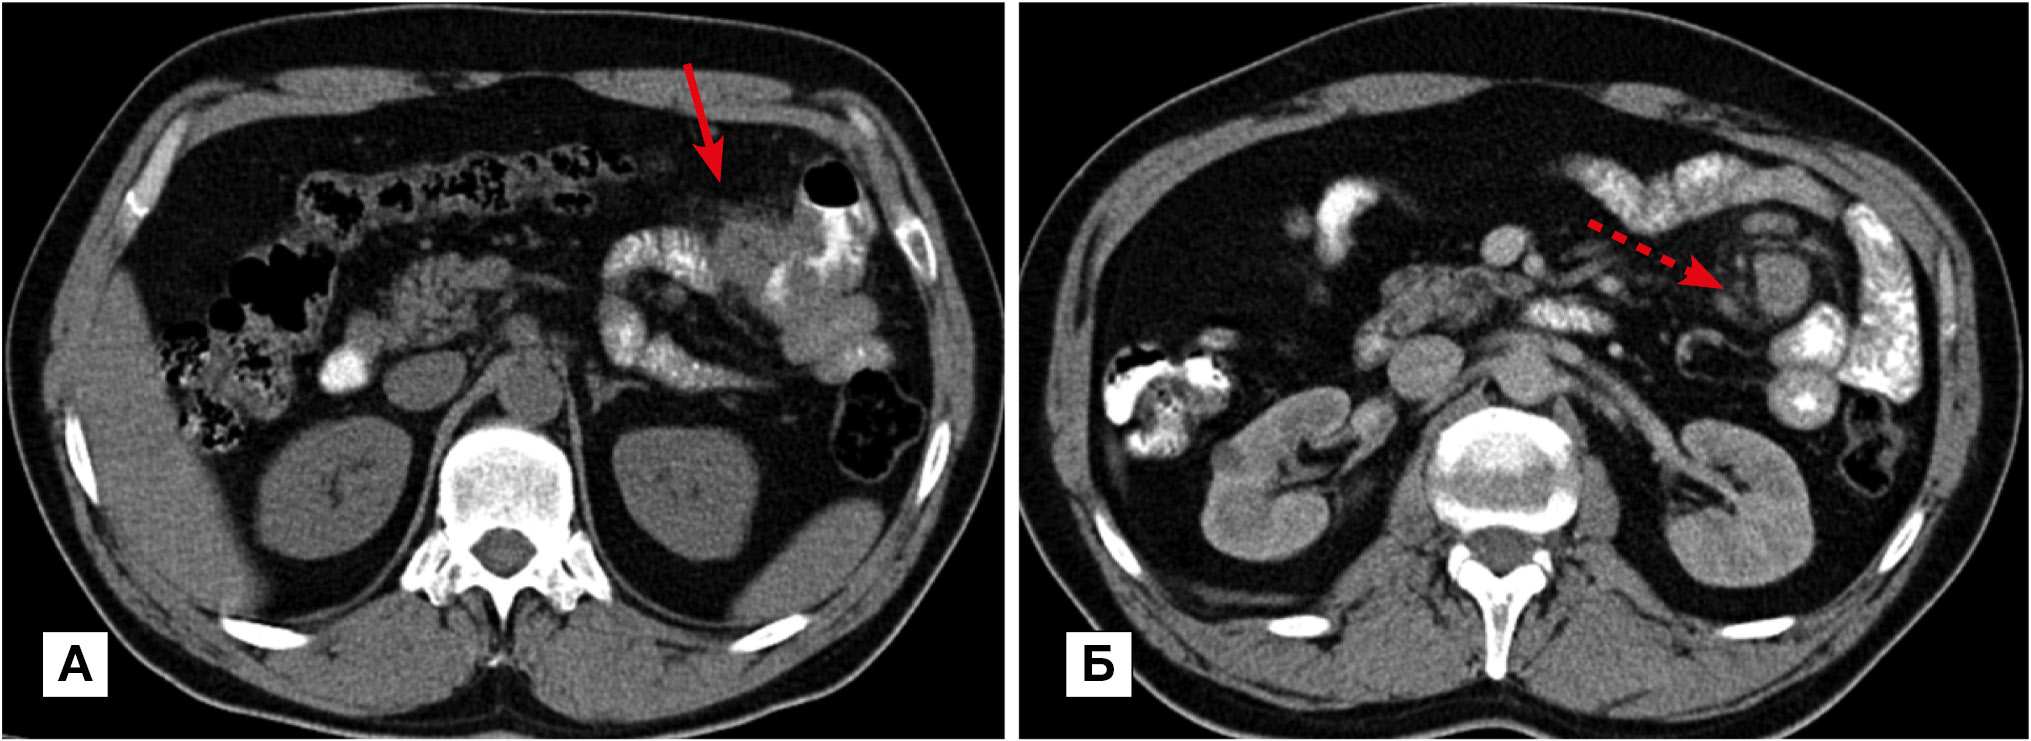

Рис. 2. Больная, 34 года. МСКТ: болезнь Крона, множественное поражение тонкой и толстой кишки. Артериальная фаза контрастного усиления. Фрагменты аксиальных томограмм

Примечание. Определяется сегментарное утолщение стенки ТК (стрелки) и нисходящей ободочной кишки (пунктирная стрелка). При контрастном усилении наблюдается трансмуральное контрастное усиление стенки и усиление сосудов брыжейки (обозначено кругом).

В фазу ремиссии болезни Крона контрастирование стенки характеризовалось трансмуральным утолщением и слоистостью на фоне развития фиброзных изменений в подслизистом слое и повышенного контрастного усиления слизистой оболочки (рис. 3, А) или отложением жировых включений в подслизистом слое (рис. 3, Б).

Рис. 3. МСКТ: болезнь Крона, стадия неполной ремиссии

Примечание. А — артериальная фаза контрастного усиления: определяется трехслойная структура стенки терминального отдела подвздошной кишки (стрелка) за счет развития фиброзных изменений в подслизистом слое и повышенного контрастного усиления слизистой оболочки. Б — больная в возрасте 67 лет: болезнь Крона, стадия ремиссии; нативное исследование: трехслойная структура стенки терминального отдела подвздошной кишки объясняется отложением жировых включений в подслизистом слое (стрелка).